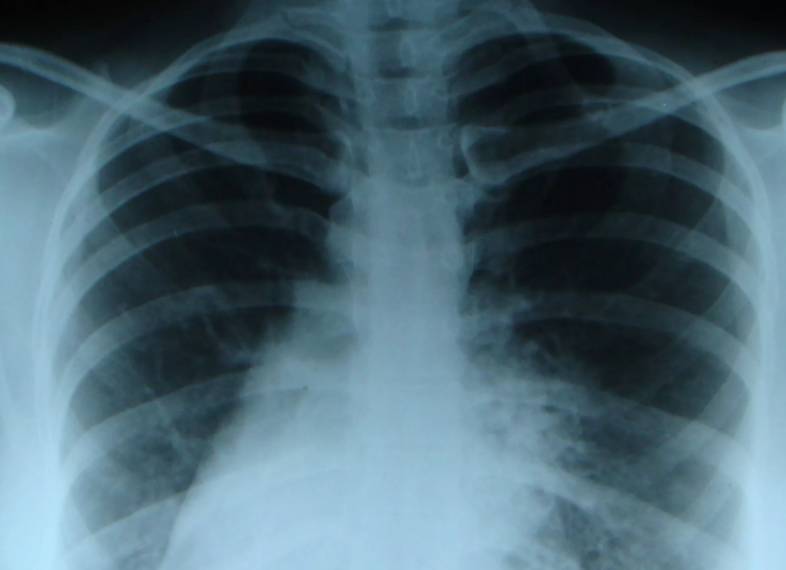

Подозрение на декстрокардию может возникнуть во время аускультации или пальпации при медицинском обследовании. Для более точной диагностики этого состояния могут быть использованы следующие методы:

- УЗИ и рентгенография сердца и сосудов;

Выбор метода обследования зависит от тяжести состояния и наличия сопутствующих заболеваний. Врач также проводит осмотр пациента, собирает анамнез, измеряет артериальное давление и обращает внимание на цвет кожи. Кроме того, педиатр оценивает уровень умственного и физического развития ребенка.